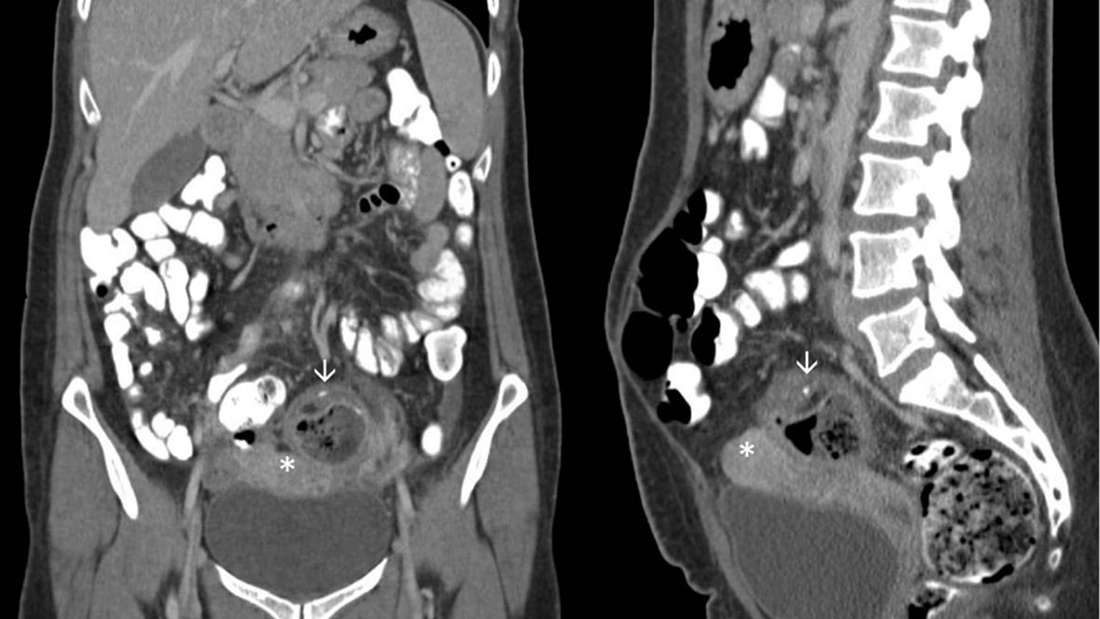

Egy 32 éves nőt a Michigan állambeli rochesteri városi kórházba vittek erős hasfájdalmakkal. Bélrendszeri problémákkal kezdték vizsgálni, mikor rábukkantak a jelentősen megnagyobbodott petefészekre, amely ráadásul hozzá volt nőve a medence és a vastagbél falához.

Először leválasztották a petefészket, amely mellett egy hatalmas ciszta volt. Az orvosok úgy írták le, hogy nagyon rossz szaga volt feltehetően egy szuperinfekció (kórokozóváltással járó felülfertőződés) eredményeként.

Aztán mikor feltárták a cisztát, zöldséget találtak benne. A tanulmány szerzői azt mondják, hogy az étel valószínűleg a nő belén lévő lyukon keresztül szivárgott ki, amely később „spontán zárult”, mivel a műtét során nem találtak semmiféle perforációt. Majd az anyag innen valahogy bekerült a petefészekbe.